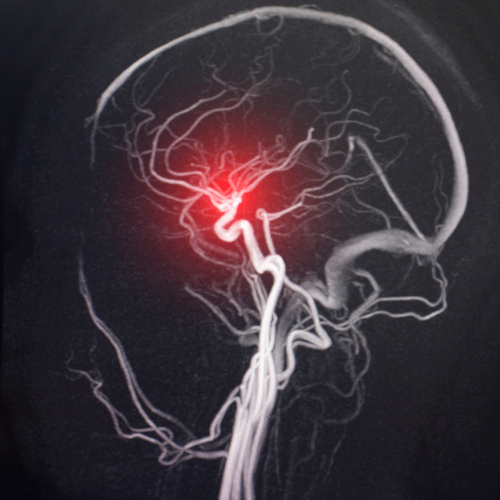

Santral Sinir Sisteminin Basit Anatomisi Sinir sistemi genel olarak santral sinir sistemi ve periferik sinir sistemi olarak ikiye ayrılır. Santral sinir sistemi beyin, beyin sapı, beyincik ve omurilikten oluşur. Periferik sinir sistemi ise omurilikten çıkan spinal sinirler ve otonom sinir sisteminden oluşur. MENİNKSLER (BEYİN ZARLARI) Beyin ve omurilik, kendisini darbelerden koruyan kranium ve omurga kanalı […]